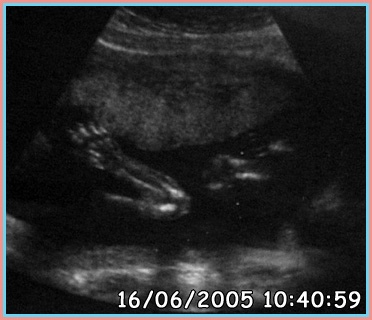

29/04/2005

Wk 14 - The Scans

As of 29/04/2005 we have three scans done at Burnely General Hospital. I have tried to keep them as clear as possible. Since any bright light or scanning would turn the photos black.

I have also marked out each section on a second picture showing you what is what, as they can be confusing to look at.

The scans have been placed in order they have been taken.

Plain Scan